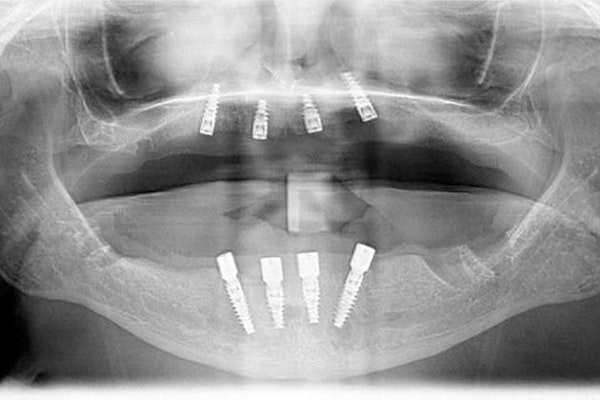

For example, Dr. Pinnix and Dr. Betancourt can utilize our CAD/CAM system to take digital impressions and create 3D images of your smile. These images allow for more precise planning and conservative treatment. We can also take digital X-rays to accurately visualize the supporting structures of your smile while designing your implant treatment plan.